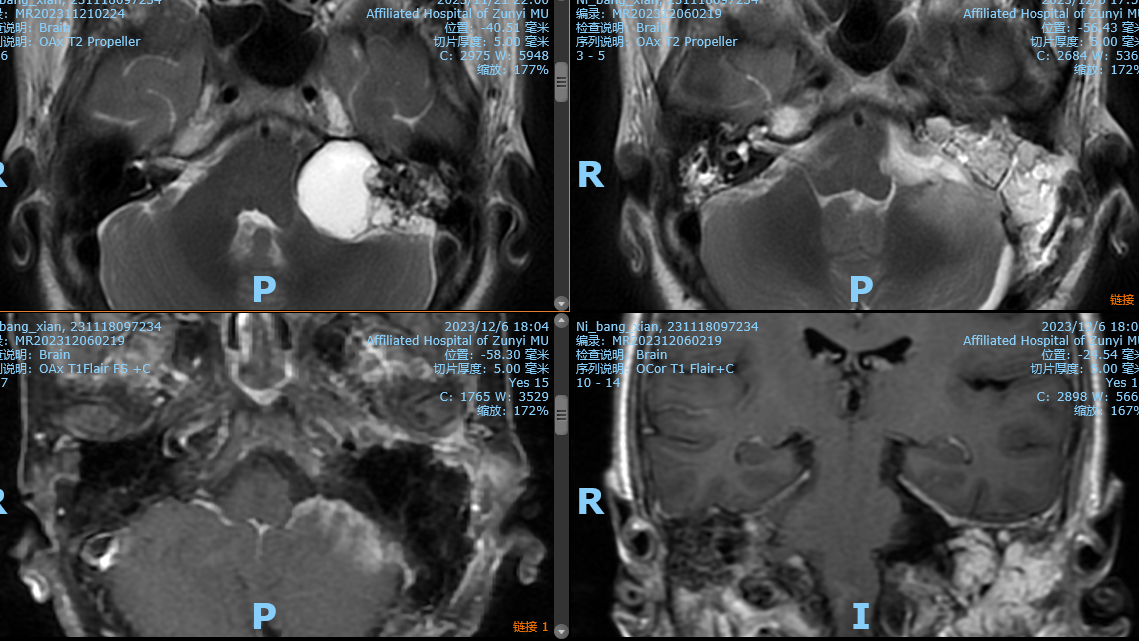

术后复查影像

阅片后考虑为左侧内淋巴囊肿瘤,侵犯岩骨,破坏面听神经,手术方案选择:左侧乙状窦前入路,窦前入路切除CPA区肿瘤,同时做岩骨次全切,术中发现面神经破坏,截取左侧耳大神经作为桥接神经,行左面-舌下神经端侧吻合,关颅后发现左侧外耳道与颅内相通,脑脊液缓慢流出,又在神经内镜下行外耳道缝扎术,术后2周出院,无脑脊液耳漏、鼻漏。术后病理后免疫组化证实为内淋巴囊肿瘤,ki-67达20%。

ELST的预后及随访:根据ELST有局部复发倾向的特点,我们建议术后3个月、6个月、1年定期随访并行增强MRI检查。随访过程中,患者若出现不明原因的腰背疼痛、马尾综合征及神经根痛等症状,应行脊柱影像学检查以排除脊柱转移的可能。局部复发及远处转移的ELST患者,经过评估手术风险小,能够达到病灶全切除者仍应首选手术切除,其次考虑放疗。